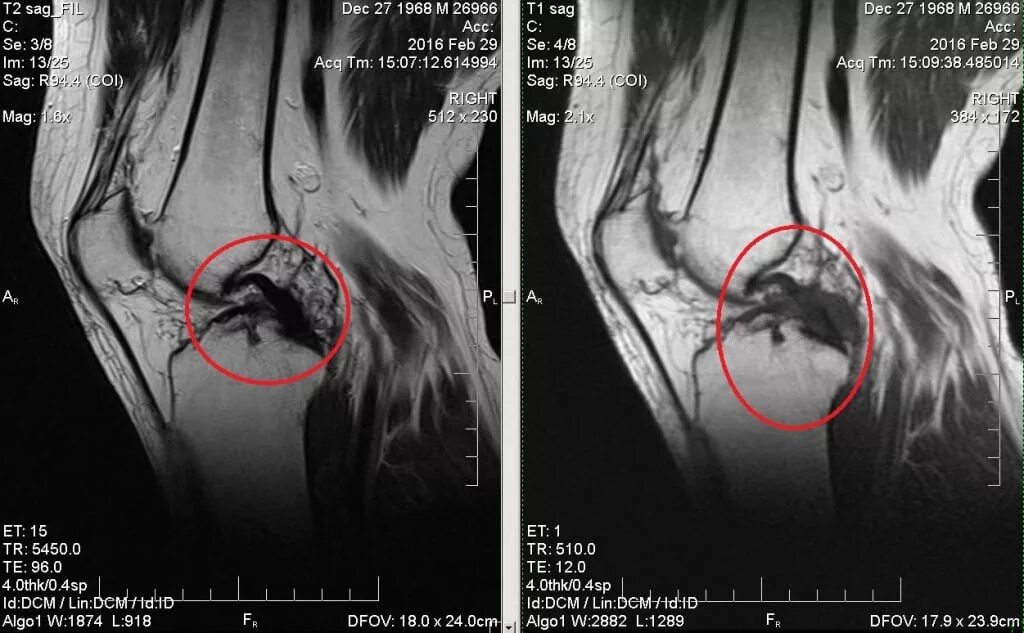

Мрт коленного сустава времени